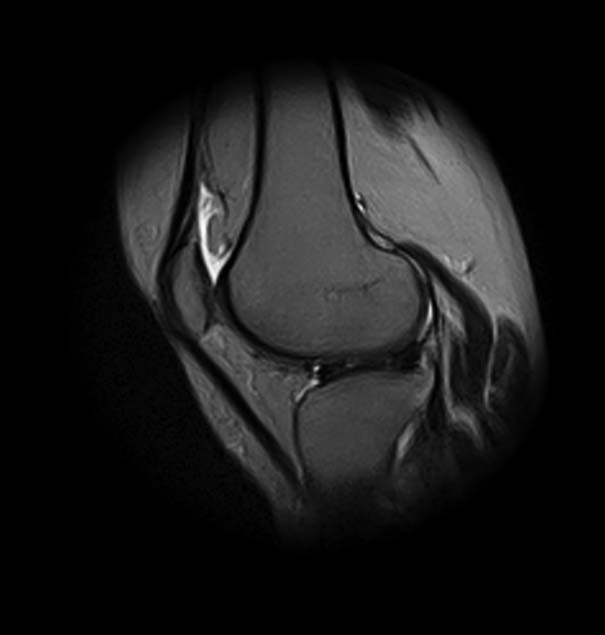

[Ortho] Показания для артроскопии

1. травма 5 лет назад - "ударилась коленом", с тех пор боли в суставе

3. стандартные рентгенограммы с небольшими изменениями - сужение

медиальной суставной щели

4. вес пациентки 80 кг, рост 165

5. сустав клинически стабилен